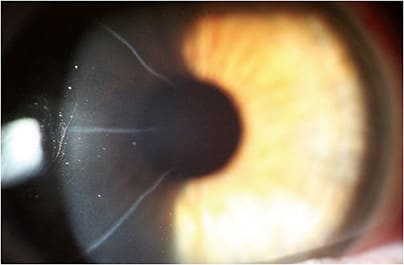

Entering MRx in both eyes is a low level of hyperopia with astigmatism in both eyes. Anterior segment exam is remarkable for 8 cut RK OD and 16 cut RK OS (Figures 5 and 6). Heidi has visually significant anterior cortical cataracts in both eyes. Posterior segment exam is unremarkable in both eyes.